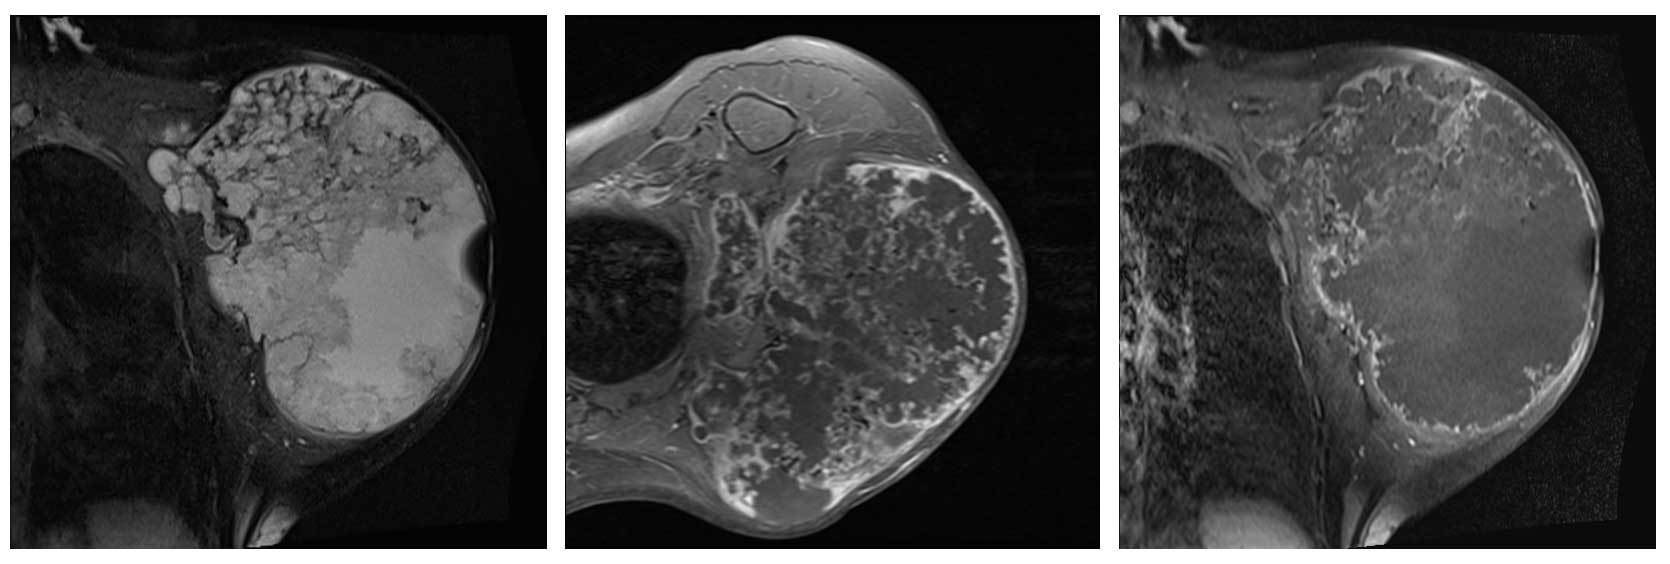

Ameliyat Öncesi: MR’da tümörün heterojen olup nekroz alanları içerdiği görünmekte.